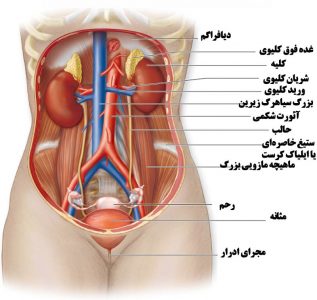

عکس کلیه در بدن. اگر پشت یا پهلوی شما آسیب ببیند مثل برخورد ضربه ممکن است فکر کنید که کلیه هایتان درد می کنند. مقدار و نسبت ترکیب این اخلاط در بدن هر شخصی و در اندامهای. کلیه گ رده ها1 از اندام های درونی بدن انسان به صورت یک جفت عضو لوبیایی شکل در طرفین ستون فقرات روی جدار پشتی شکم و بیرون از حفره صفاق قرار دارند. ک لیه ق لوه میز یا گ رده یکی از اندام های درونی بدن انسان و برخی دیگر از جانداران است.

وظایف کلیه ها در بدن. و دخالت این چهار مایع را در کلیه حالات بدنی. شکل زیر عکس واقعی کلیه انسان را نشان می دهد. اگر عملکرد آن ها کم شود نیاز به دیالیز پیدا می کنند.

در هر ساعت کلیه های بدن انسان حدود ۷ لیتر مایع را از خون جدا می کنند این مایع را تصفیه کرده و مواد مفید و سودمند آن را به خون بازمی گردانند و مواد مضر آن را از راه میزنای به مثانه می فرستد تا دفع شوند. کجای بدنتان درد می کند مراجعه کنید آیا کلیه تان درد می کند درد کلیه در اثر عفونت کلیه یا آسیب رسیدن به آن ایجاد می شود. اما کار و وظیفه کلیه ها در بدن چیست بیا یاد بگیریم. زمانیکه کلیه ها بدرستی فعالیت کنند مواد زائد از بدن داخل ادرار ترشح می شوند همچنین کلیه ها در تنظیم سایر مواد معدنی در بدن مانند.

کلسیم و فسفر که برای تشکلی استخوان لازمند کمک می کنند مواد. کلیه ها با تولید ادارد در دفع مواد زاید تعادل الکترولیتی تنظیم هورمونی تنظیم فشار خون و هوموستازگلوکز نقش دارند. آناتومی کلیه انسان در بدن انسان به این شکل است که کلیه ها دو عضو لوبیایی شکل در دستگاه ادراری بوده و به دفع مواد زائد به صورت ادرار کمک می کنند. یکی از مهم ترین وظایفی که کلیه ها در بدن بر عهده دارند پاک کردن و تصفیه خون از زباله هاست.